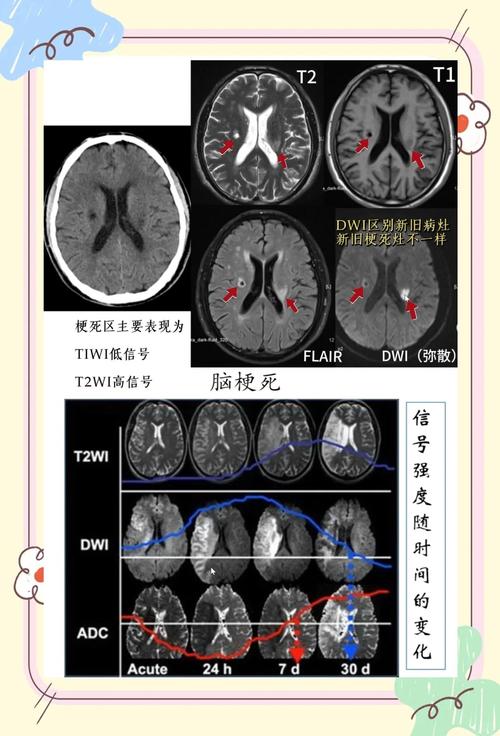

MRI可以提供T1加权像、T2加权像、FLAIR(液体衰减反转恢复)、DWI、PWI(灌注加权成像)等多个序列,通过综合分析这些序列,医生不仅能判断是否存在脑梗,还能评估梗死的范围、时间(是新发还是陈旧)、以及脑组织的血流灌注情况,这对于指导治疗(如是否适合溶栓)至关重要。

- 关键点:ADC(表观弥散系数)图! 这是鉴别DWI高信号是“真脑梗”还是“假病灶”的关键。

- 急性脑梗: 细胞毒性水肿,水分子运动受限,DWI高信号,ADC低信号。

- 肿瘤、脓肿等: 细胞外水肿为主,水分子运动相对自由,DWI高信号,但ADC也是高信号(或等信号)。

- 血管源性水肿(如PRES): 同样是ADC高信号。

- 一个经验丰富的放射科医生一定会将DWI与ADC图进行对照分析。

- 新旧病灶并存: 患者既有新发的急性脑梗,又有陈旧的小软化灶,如果阅片不仔细,可能会漏掉新病灶或将陈旧灶误认为新病灶。